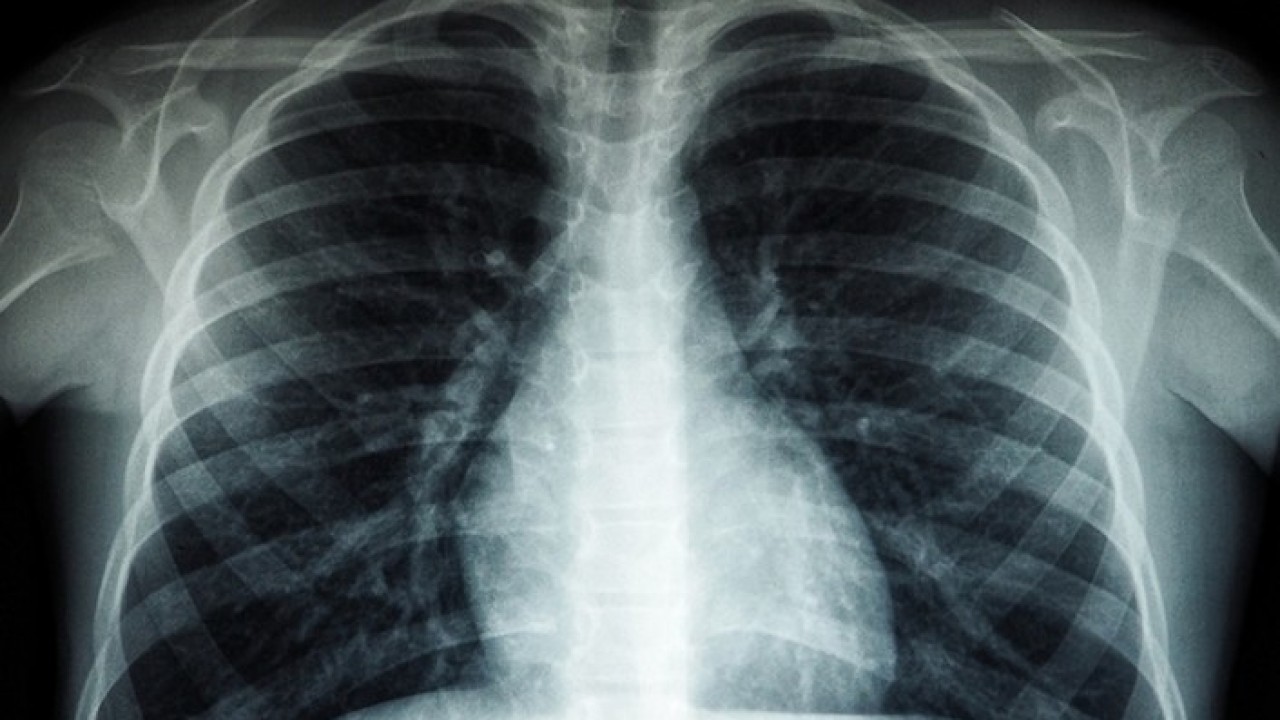

Röntgen ve ileri tetkiklerle hastalığın tespit edilebildiğinin altını çizen Özkara, Türkiye'de veremin 6 ay kullanılan ilaçlarla kolaylıkla tedavi edilebildiğine ve tüm tedavi masraflarının da devlet tarafından karşılandığına dikkati çekti.